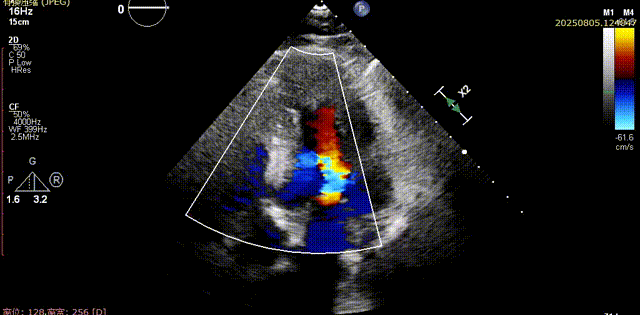

术前胸骨旁长轴切面可见流出道结构良好,五腔心切面可见主动脉瓣少中量反流

流出道结构观察

五腔心切面观察